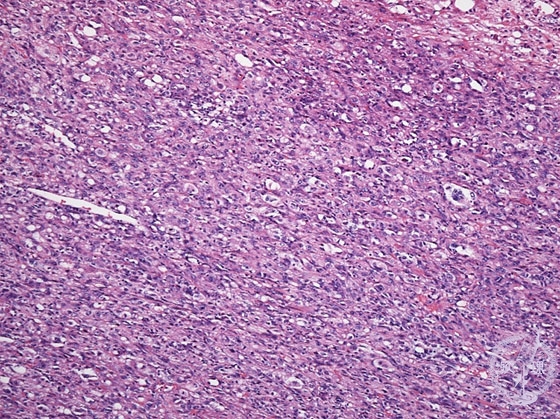

Histology (HE stain, low power): Spindle-shaped tumor cells with oval nuclei that proliferate in a solid fashion.